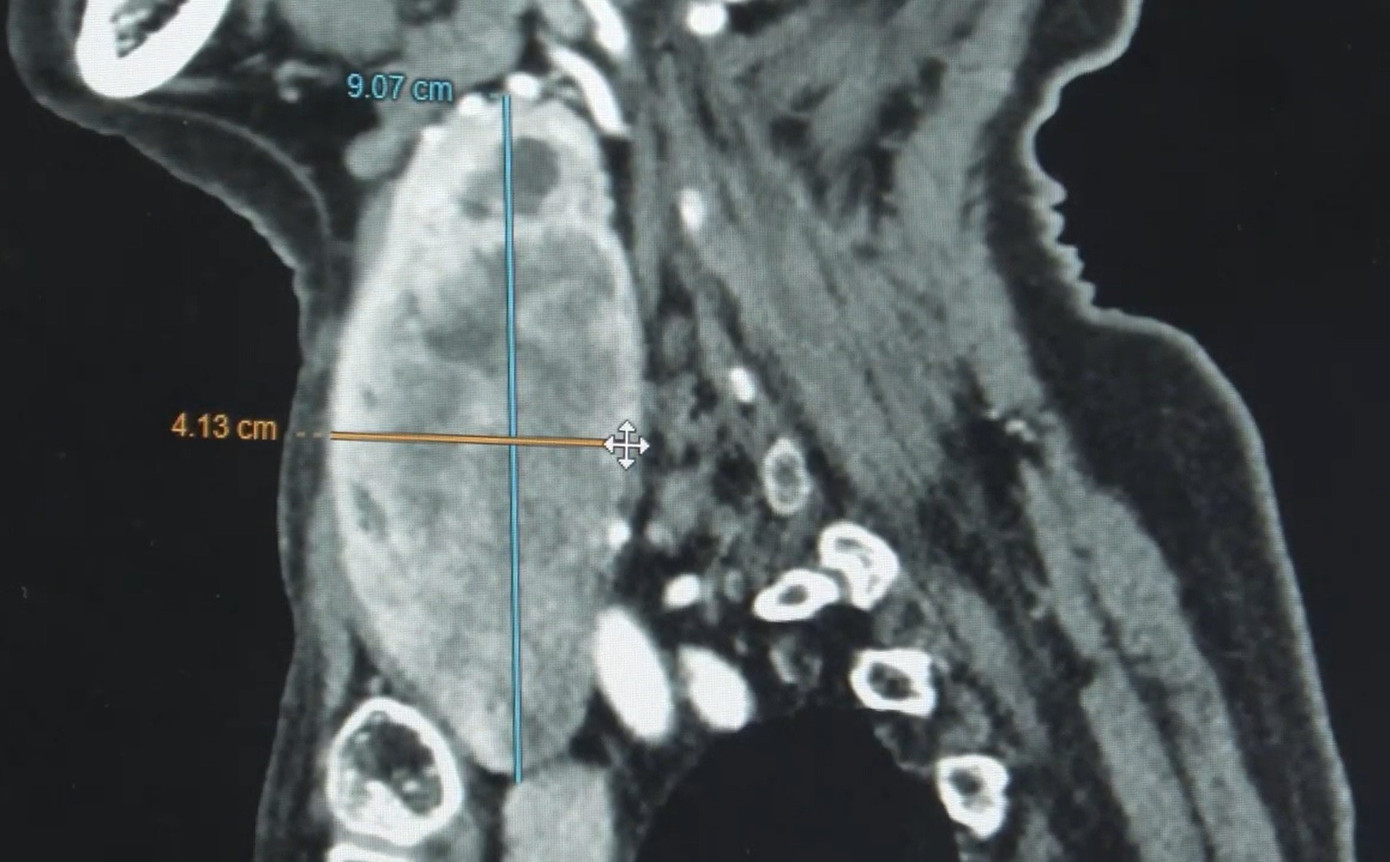

Khối bướu phát triển lớn sau 5 năm chung sống khiến bệnh nhân đối mặt với nguy hiểm

BS Thành cho biết, kết quả kiểm tra hình ảnh cho thấy, bệnh nhân bị bướu giáp đa nhân hai thùy khổng lồ, thùy trái kích thước 9 cm. Khối bướu lớn lộ ra ngoài, chèn ép thực quản và dây thần kinh thanh quản.